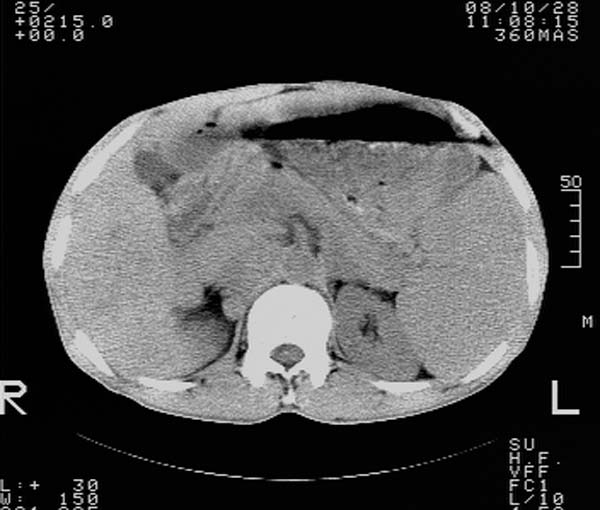

m,65y。半年前发现颈小结节,逐渐增多增大,现双侧耳后、颌下及颈部表浅淋巴肿大。胸片示双肺门增大。外院曾穿刺诊断为淋巴结核。在我科作胸腹部ct,我们觉得外院病检有误。现将图像上传请战友讨论。

纵隔内及腹膜后广泛淋巴结肿大,脾大,肝内似可见低密度影,结合病史半年前发现颈小结节,逐渐增多增大,现双侧耳后、颌下及颈部表浅淋巴肿大。考虑淋巴瘤。

我们也是首先考虑淋巴瘤。只是外院病检报告是结核。让人迷惑。肝左叶多发低密度占位,没增强不好定论。

纵隔,双肺门腹膜后多发淋巴结重大,非融合,肝脾轻度肿大,双肺野弥漫性小结节;考虑淋巴瘤,结节病可能性

纵隔内,双肺门、腋窝及腹膜后多发肿大淋巴结影,肺内小结节影,肝脾体积增大,支持淋巴瘤。肝内多发低密度影,考虑小囊肿。

纵隔内,双肺门、腹膜后多发肿大淋巴结影及颈部淋巴结肿大,肝脾体积大.结合临床,淋巴瘤可能性大。